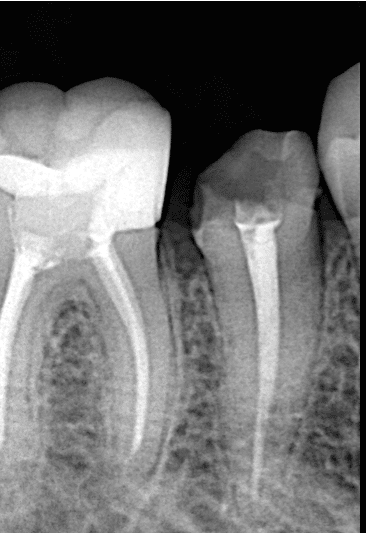

Initial x ray

After preparing the tooth